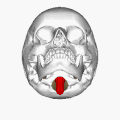

Череп знизу. Великий отвір і довгастий мозок (показаний червоним кольором).